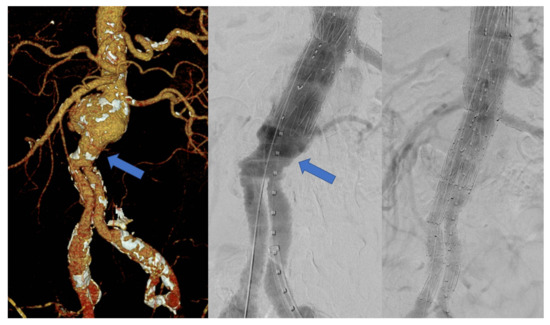

3.2. Stent Graft Design and Procedure

3.3. Technical Success and Early Outcomes